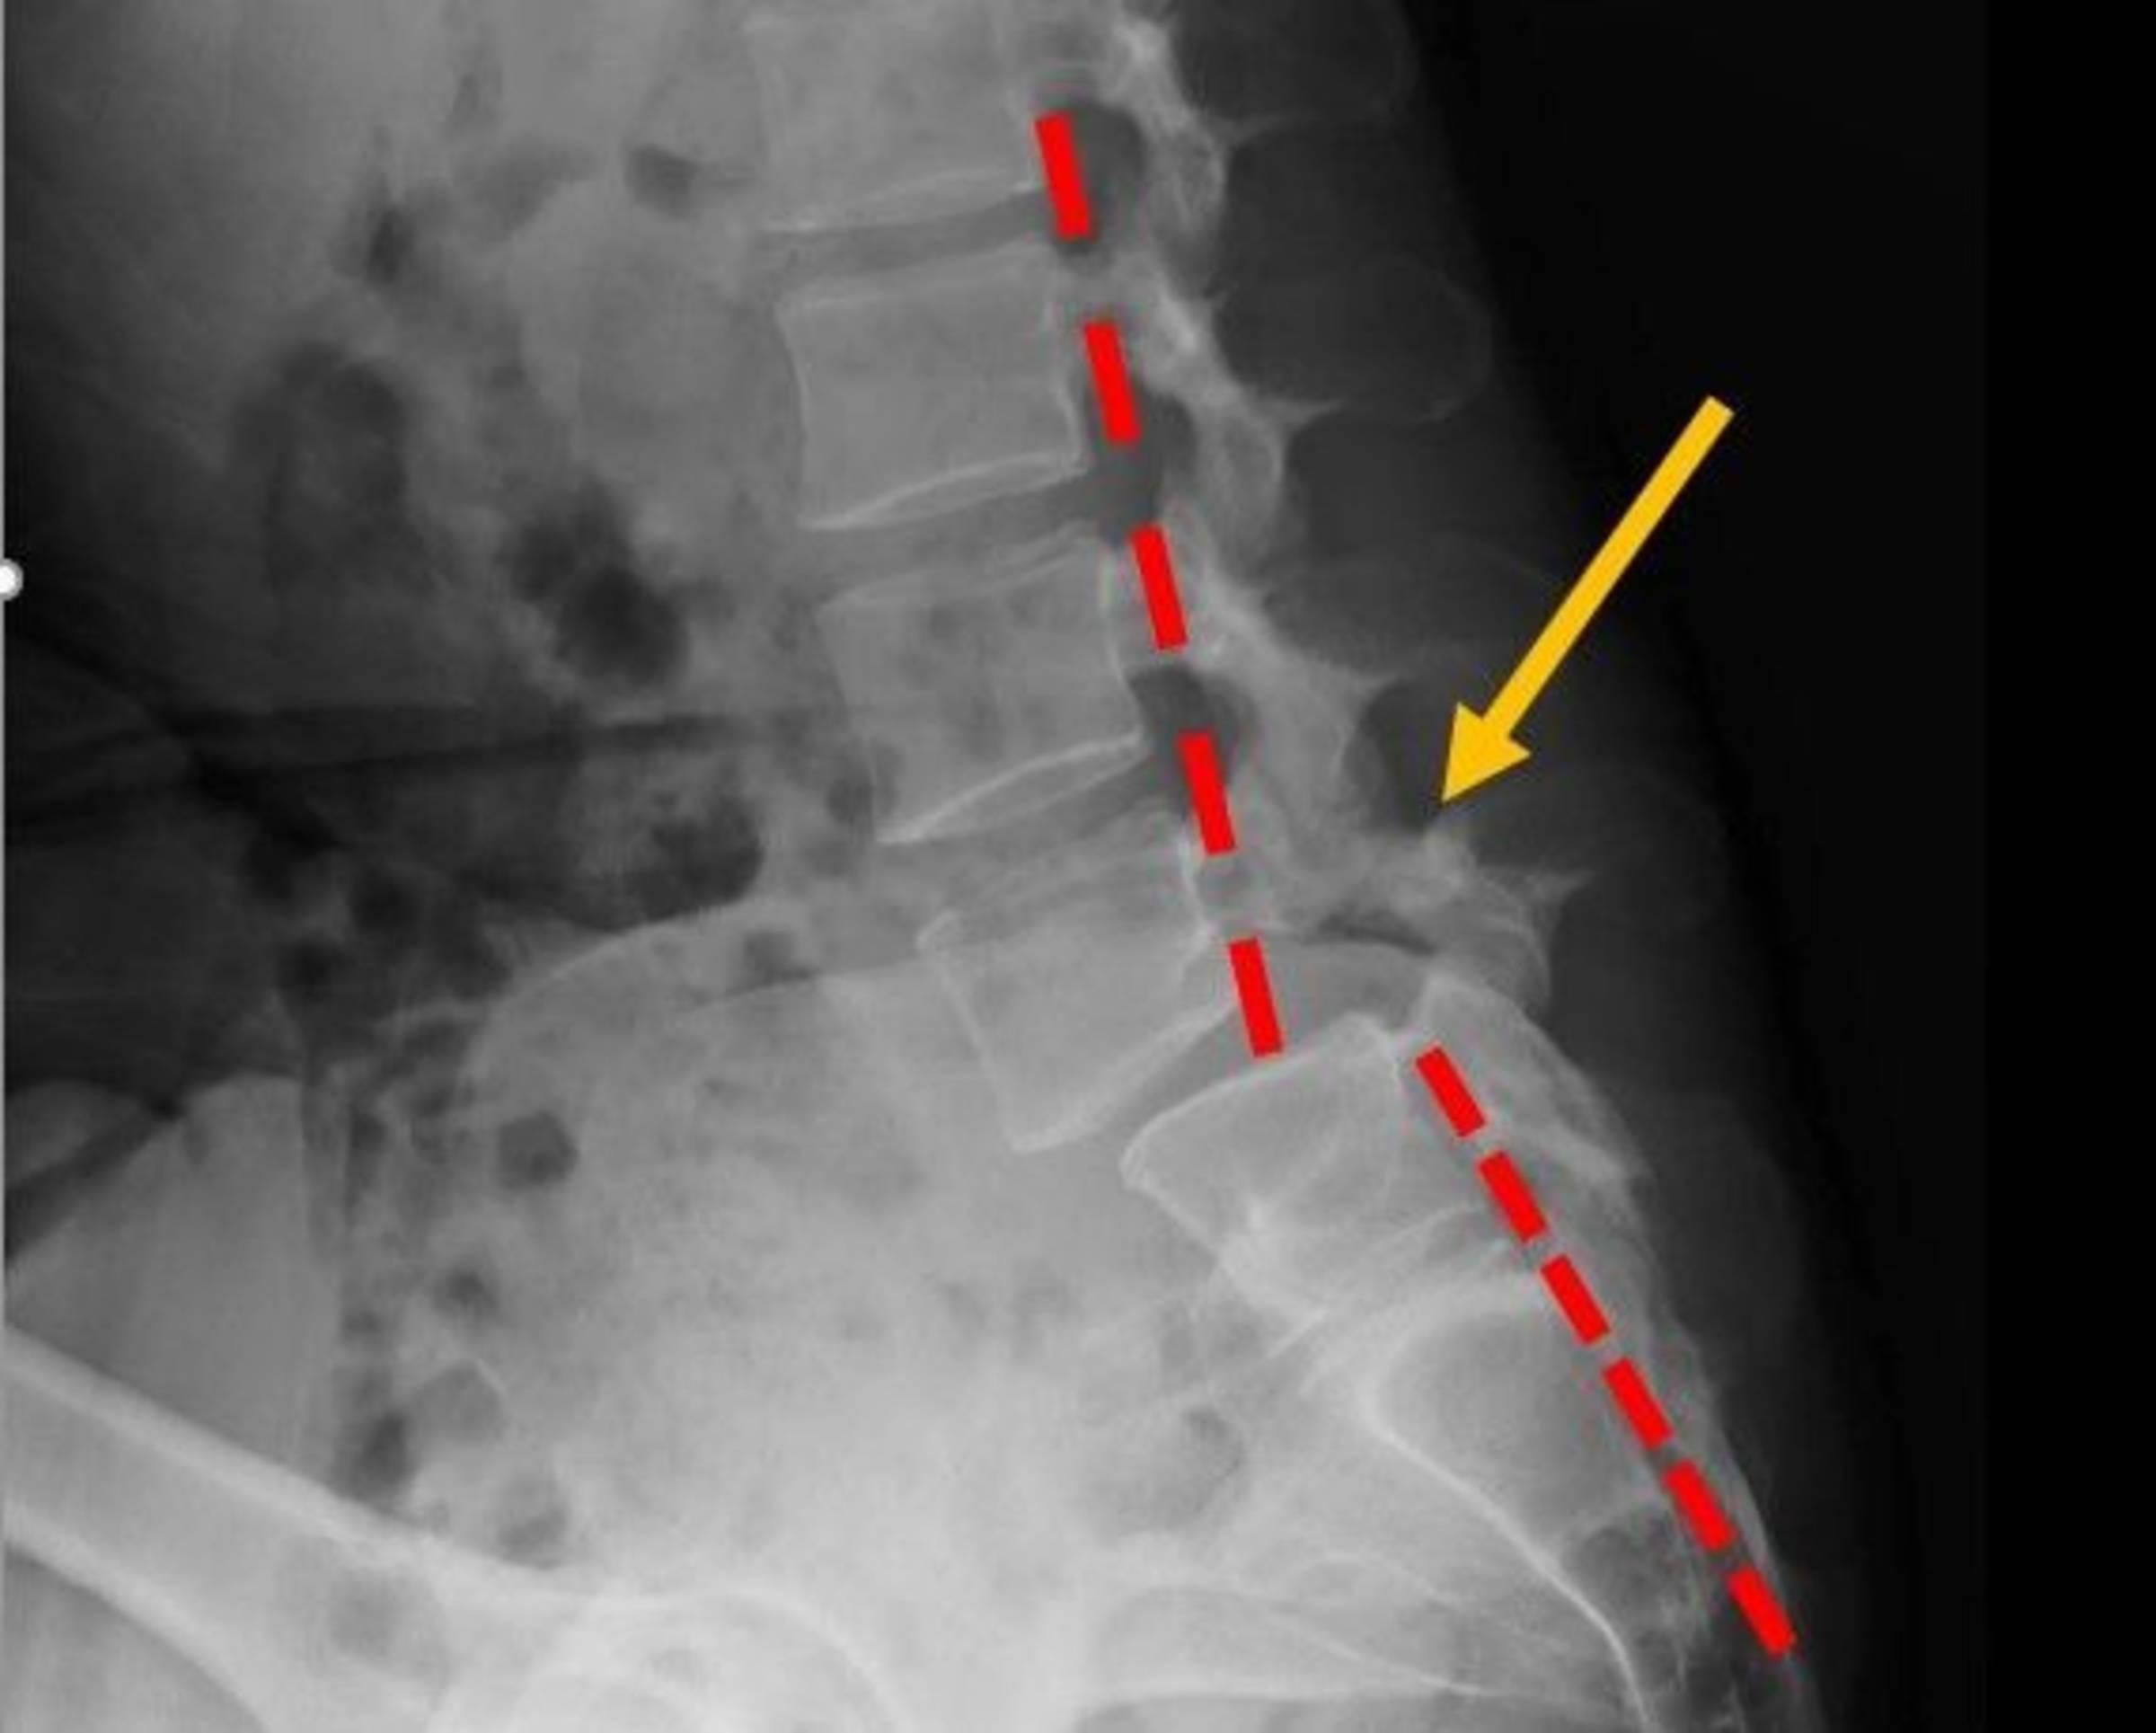

脊椎滑脫會壓迫脊椎神經導致腰背痛。